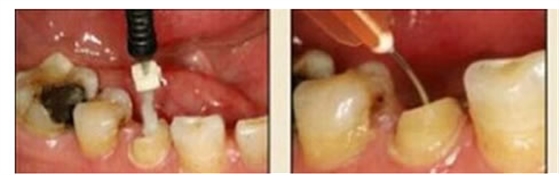

10.毛刷的選用

圖20:毛刷應(yīng)用(錯(cuò)誤) 圖21:根管專用毛刷

市場(chǎng)上毛刷的種類繁多,臨床應(yīng)用比較雜亂。冠部牙體組織或各種修復(fù)體涂抹粘接劑時(shí),由于粘接面視野清晰、范圍大,對(duì)毛刷的選擇一般無(wú)嚴(yán)格要求,臨床大多使用圓球形或鬃束狀毛刷;纖維樁修復(fù)時(shí),由于根管樁道有深度且視野差,以上兩種毛刷很難伸入狹窄的樁道深部,無(wú)法保證粘接劑在整個(gè)樁道內(nèi)壁被均勻地涂抹(圖 20)。纖維樁粘接時(shí)應(yīng)使用根管專用微型毛刷(圖 21),其形態(tài)和長(zhǎng)度與樁道吻合,毛刷頭部可彎曲控制,可到達(dá)較深的根管底端,有利于粘接劑的均勻涂布。某些根管毛刷采用納米級(jí)刷毛,根管涂擦?xí)r可進(jìn)入牙本質(zhì)小管和側(cè)枝根管,能較好地提高粘接效果。